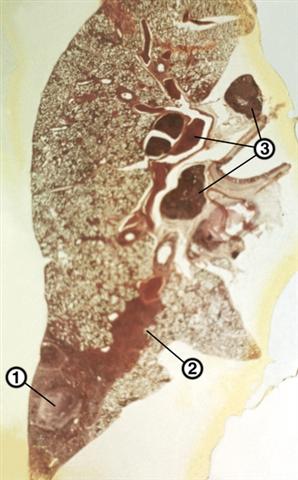

Рис. 1. Гистотопографический срез легкого и внутригрудных лимфатических узлов при первичном туберкулезном комплексе: 1 — первичный аффект в легком; 2 — лимфангиит; 3 — бронхаденит; окраска гематоксилином и эозином.